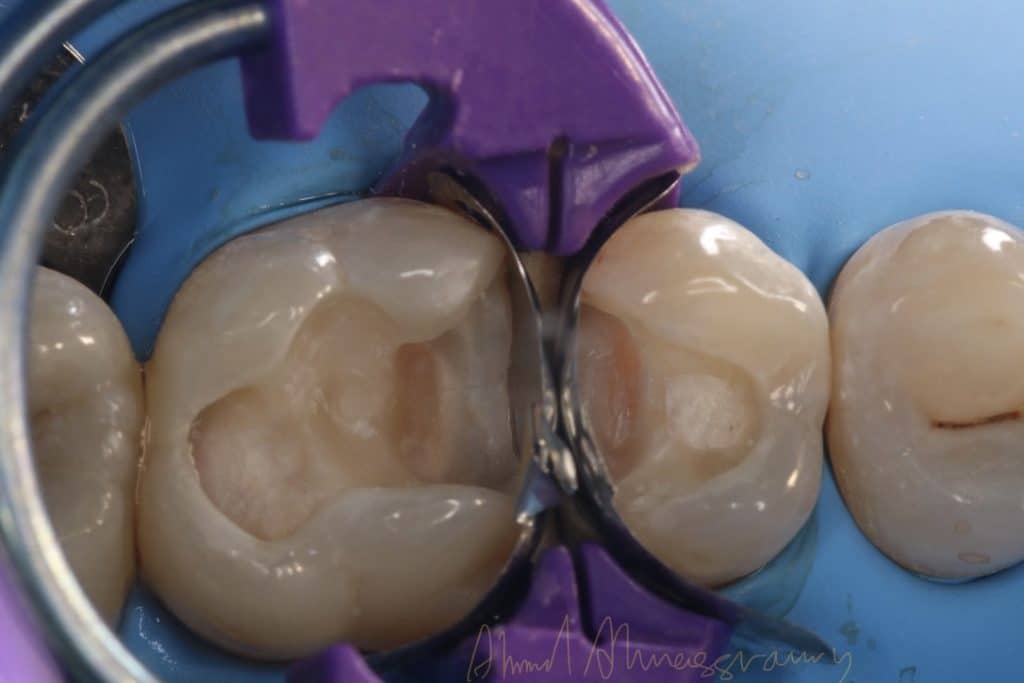

Bioclear matrix system